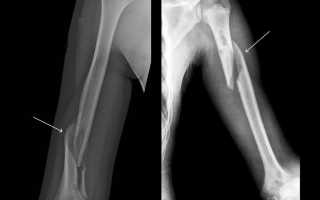

- Рентгенография;

При переломе плечевой кости со смещением отломков необходимо провести открытую репозицию, а затем надежно зафиксировать отломки с помощью погружных конструкций. Для внешней иммобилизации данного типа перелома обычно используется торакобрахиальная гипсовая повязка на срок 2-3 месяца. Чрезкостный остеосинтез с использованием аппаратов наружной фиксации показал отличные результаты в лечении пациентов с переломом плечевой кости со смещением. Процесс репозиции и срастания кости контролируется врачом с помощью рентгеновских снимков.